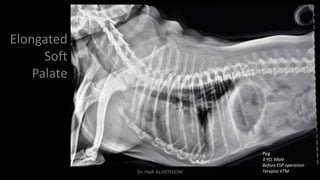

Elongated

Soft

Palate

Pug

3 YO, Male

Before ESP operation

Terapist VTMDr. Hadi ALİHOSSEİNİ